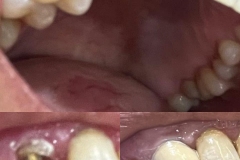

If you are self-conscious because you have missing teeth, wear dentures that are uncomfortable or don’t want to have good tooth structure removed to make a bridge, talk to your dentist to see if dental implants are an option for you.

During a root canal procedure, the nerve and pulp are removed and the inside of the tooth is cleaned and sealed. Without treatment, the tissue surrounding the tooth will become infected and abscesses may form.